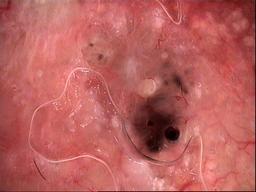

diagnosis_1 Benign

diagnosis_2 Benign melanocytic proliferations

diagnosis_3 Nevus

diagnosis_4 Nevus, Atypical, Dysplastic, or Clark

diagnosis_5 Nevus, Dysplastic

image_type dermoscopic

melanocytic True